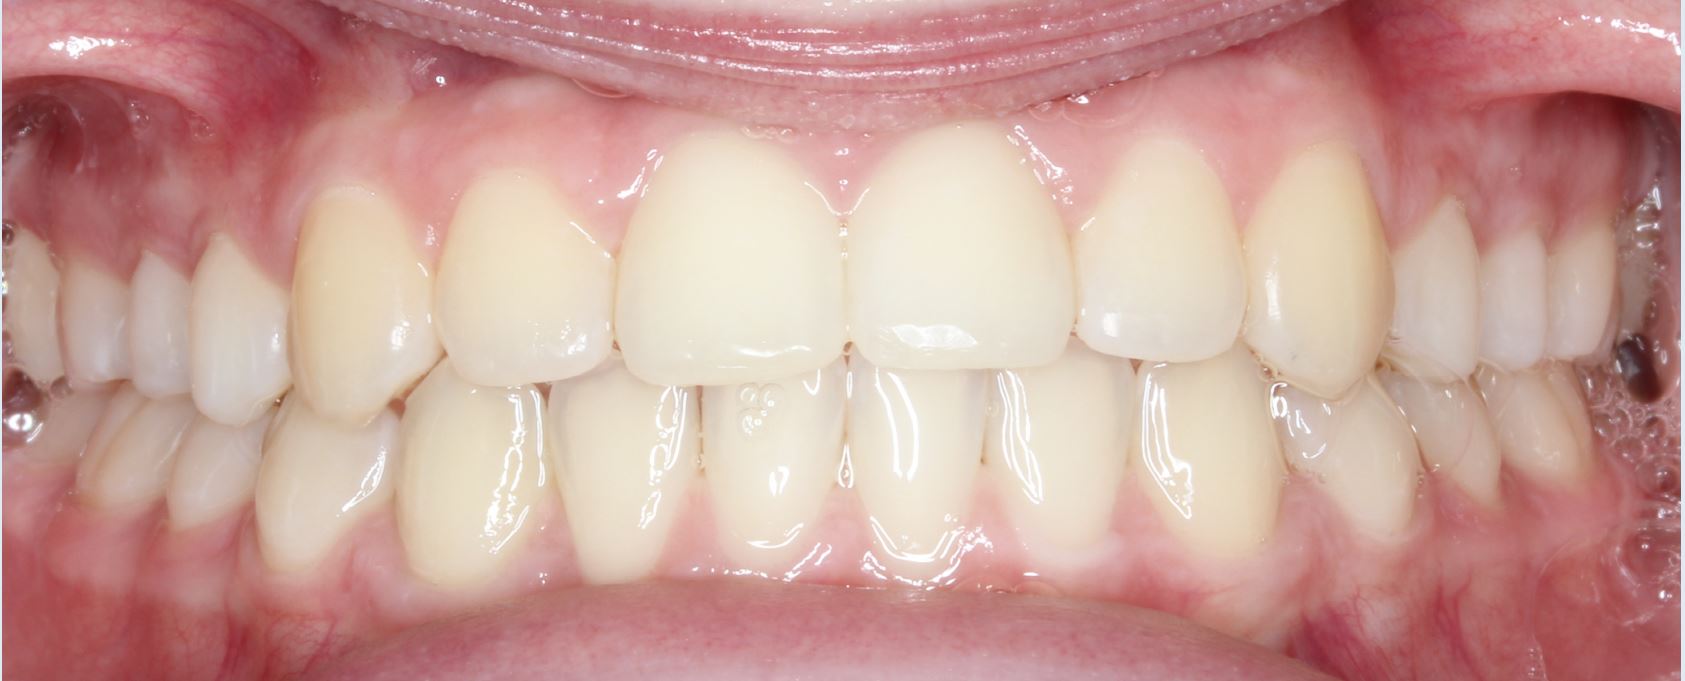

Crowding and Crossbite